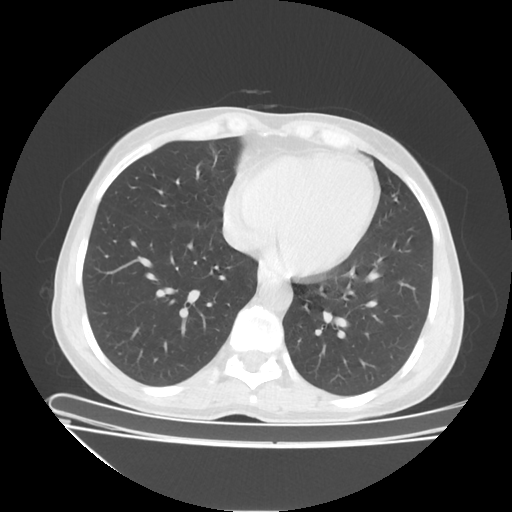

Reconstructed NATIVE CT scan (cycle consistency)

Full window (WL 1023.5, WW 4095 β†’ Low βˆ’1024, High +3071)

Lung window (WL -600, WW 1500 β†’ Low βˆ’1350, High +150)

Mediastinum window (WL 40, WW 400 β†’ Low βˆ’160, High +240)